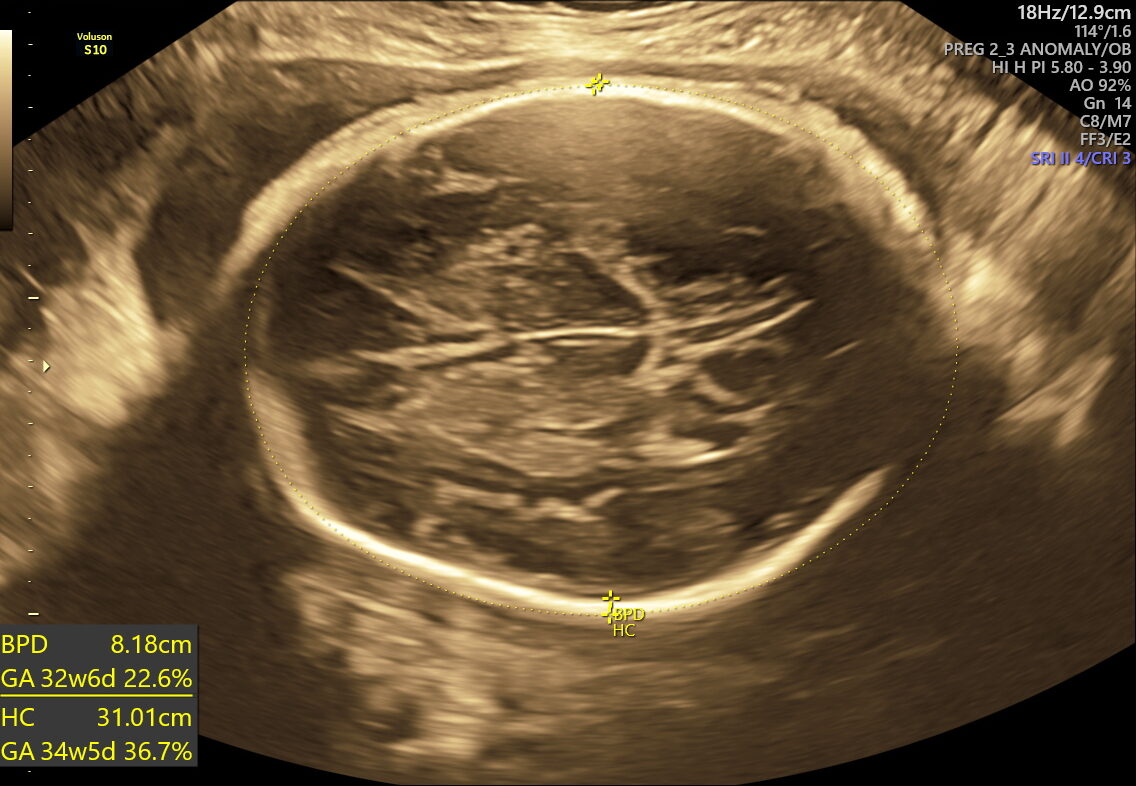

- Fetal Growth & Weight: Verifies if your baby’s size and weight meet healthy expectations for their gestational age.

This scan focuses on confirming birth readiness and spotting sudden issues that may arise close to your due date. It includes detailed Doppler studies to check blood flow in the umbilical cord and brain, ensuring your baby gets enough oxygen and nutrients.